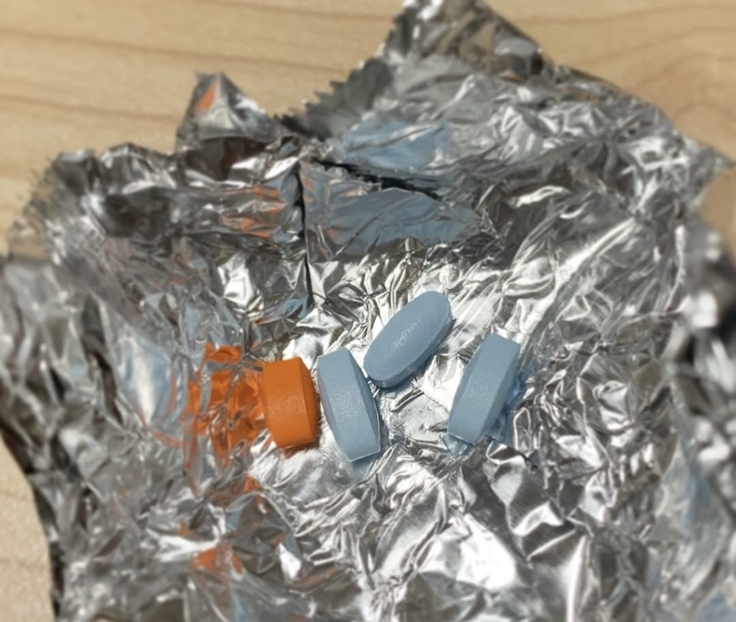

クラファン終了日が迫る中、昨日は抗がん剤治療再開 16回目の投与でした。

今日も、ちゅーるポケットで美味しくペロリ!食べてもらいました。

抗がん剤治療は、脳腫瘍をやっつける為に投与しています。

↑こちらの写真は、MRI画像です。

〇印をつけてある所がシャンティを苦しめている脳腫瘍です。

三叉神経・動眼神経です。

向かって右側よりも左側の方が大きい。

そして、とても小さいけど右側も腫瘍があると診断を受けています。

抗がん剤治療を続けていかないと、この脳腫瘍がどんどん大きくなっていきます。